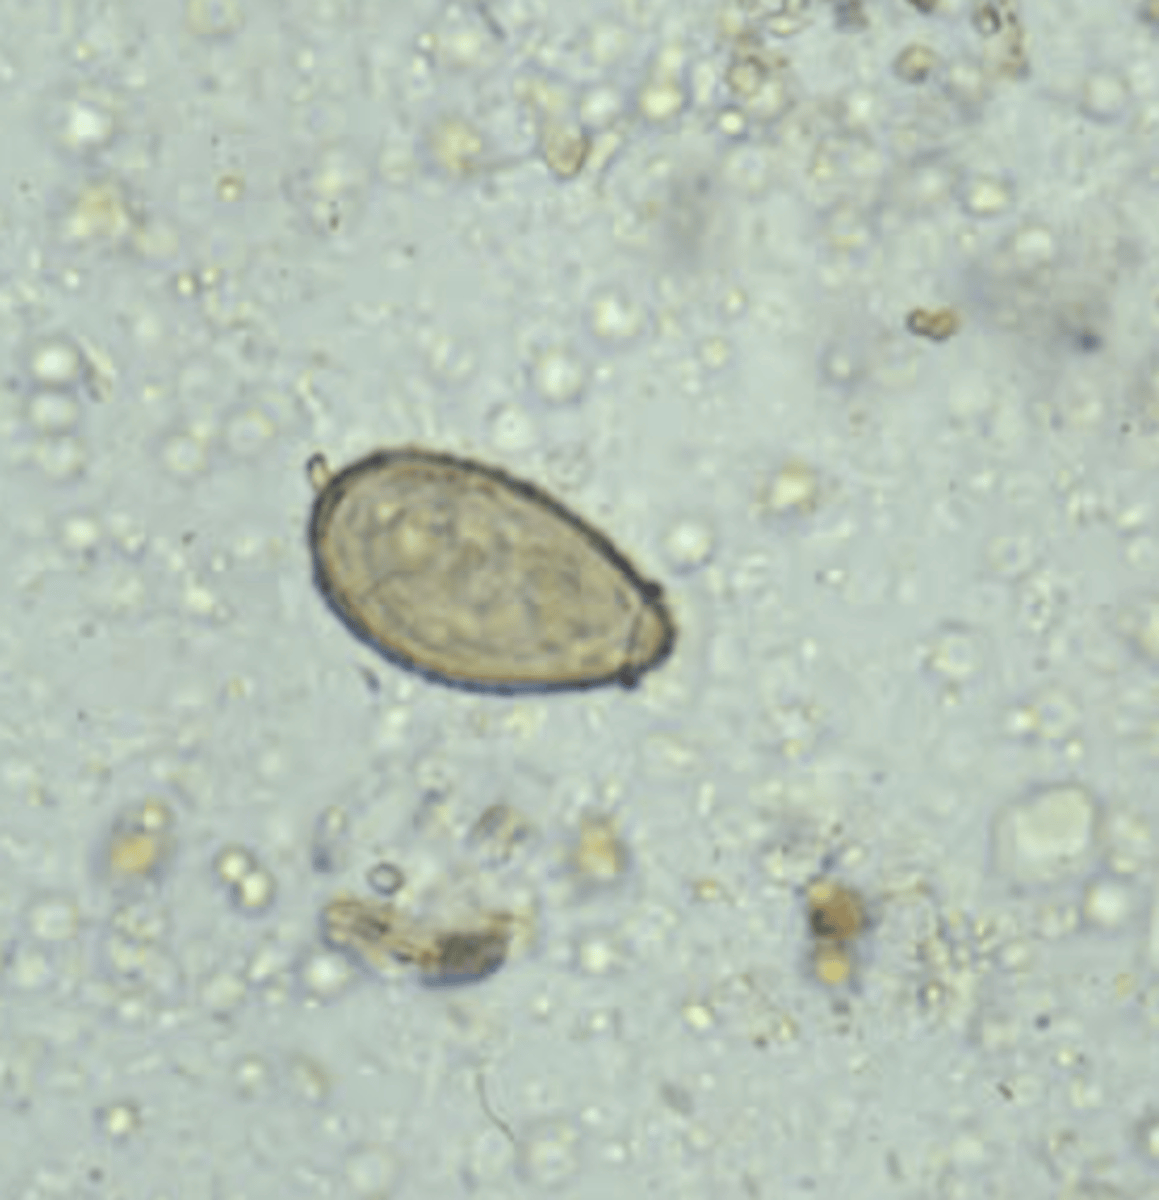

Clonorchis sinensis